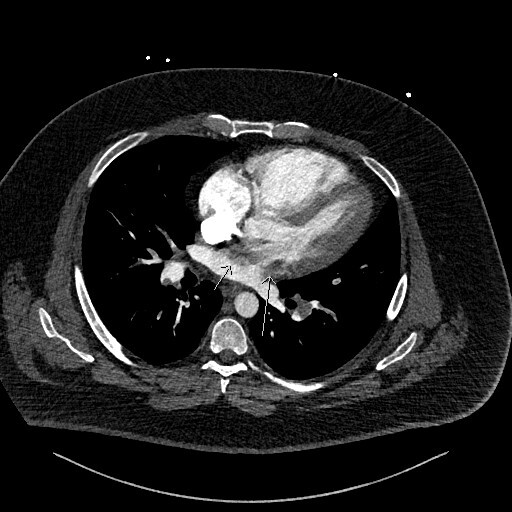

Figure 3 is the axial slice below and shows an elongated low attenuation and homogenous structure extending across a defect in the IAS into the left atrium (short arrow) and when viewed in contiguous slices was inseparable from the RA filling defect. This represented intracardiac thrombus in transit (ICTIT). There were further low attenuation, homogenous and well defined filling defects (medium white arrow) in the left atrium (LA). The radiologist also noted that the right heart chambers were enlarged compared to the left, and that both the IAS and interventricular septum (IVS) were inversely bowed toward the left – these are CTPA features that can indicate elevated right heart pressures and therefore right heart strain in the clinical context of PE.